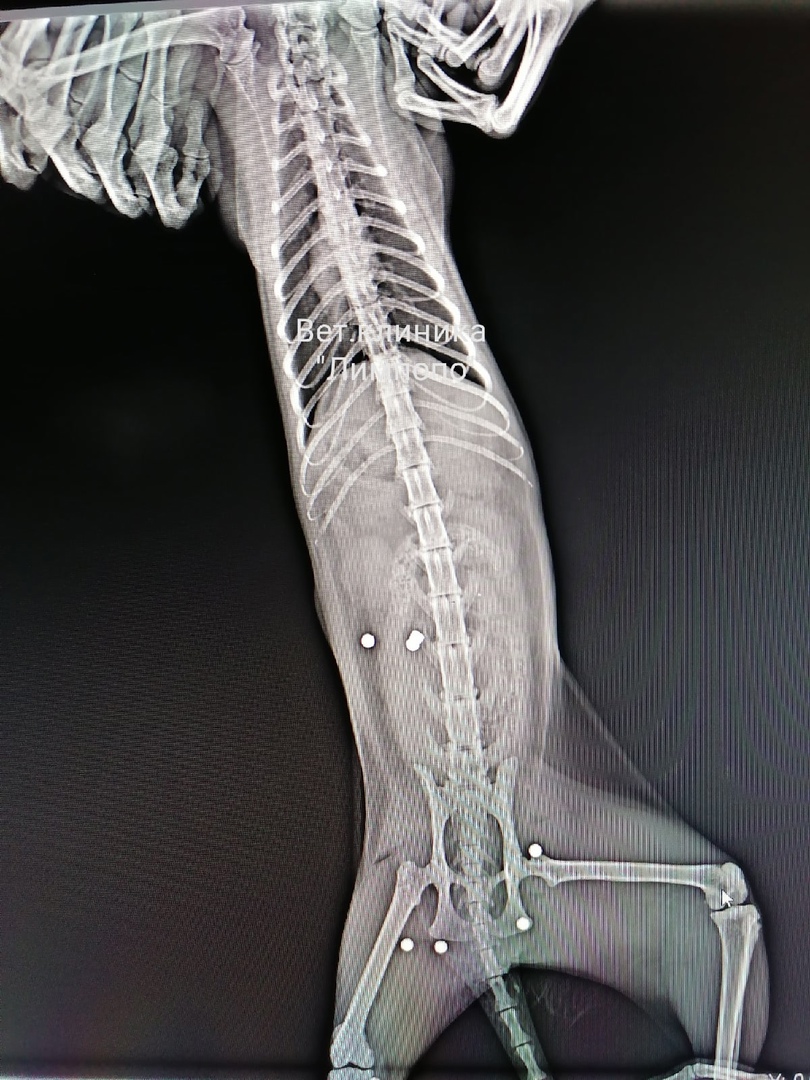

Животное с семью пулями в теле лечат в ветклинике «Лимпопо»

Сотрудники городской полиции проводят проверку по факту травмирования животного. Как рассказал «7 канал Красноярск» накануне, клиника «Лимпопо» опубликовала рентгеновские снимки животные, на которых хорошо видно, что в теле застряли семь пуль. В комментариях люди вспоминают и другие случаи жестокого обращения с питомцами и требуют ужесточения наказания за подобные проступки.